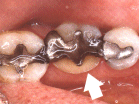

Vulling van glasionomeer vlak boven het tandvlees.

In de grote kies is, tegen de zilveramalgaamvulling aan, een compomeervulling aangebracht.